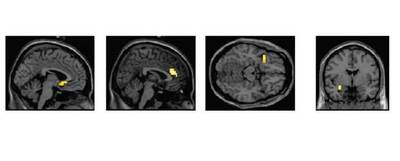

Los estudios genéticos demostraron una relación directa entre una versión poco funcional del gen de la MAOA y comportamientos agresivos en niños que habían sido severamente maltratados. Un déficit crónico del nivel normal de MAOA provoca una alteración de los niveles de algunos neurotransmisores y puede producir una hiperactividad cerebral hacia cualquier amenaza o estímulo estresante.